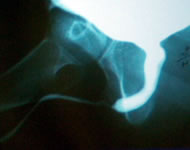

Методы

исследования:

Уретрография

Ретроградная

Нисходящая